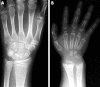

Results: Sixty five children, mostly from Black or Asian ethnic minority groups, were identified, 29 of whom had hypocalcaemic symptoms. Seventeen of these had no radiological evidence of rickets. The remainder (48 children) had radiological evidence of rickets with or without clinical signs. Symptoms and signs reverted to normal in all cases with vitamin D supplementation. All children who presented with symptomatic hypocalcaemia were aged either <3 or >10 years. There was a strong correlation between age at presentation and population growth velocity reference data.